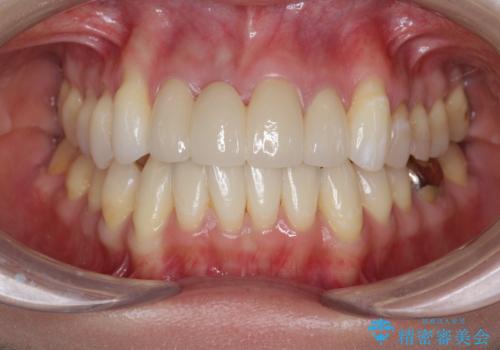

吸収し喪失した前歯、ブリッジによる審美性の回復

- 前医に前歯の吸収による抜歯の必要性を伝えられ、前歯の審美的な改善・治療を求めて来院されました。

CT撮影を行った結果、右上前歯は吸収が進み抜歯が必要な状態です、

抜歯をせず放置すると、より吸収が進み臨在する歯にも悪影響を及ぼしてしまう可能性が考えられます。

上顎4前歯は、根管治療の既往があり、虫歯も見られたことからブリッジによる治療で審美性の回復を行うとともに臨在歯の虫歯もセラミック治療を行っていきます。

- 44万円(仮歯・ジルコニアクラウン×4)費用は治療当時の料金となります

欠損部の歯ぐきの量が足りない場合は、移植を行い歯肉を増大させることもありますが、今回は仮歯で様子を見た結清掃性・審美性に問題が出なかったので行いませんでした。